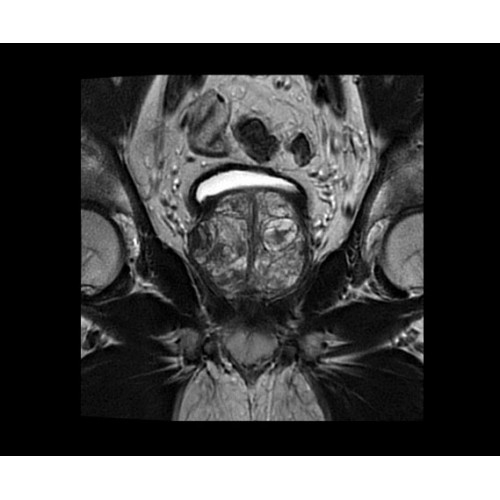

SIGNA PET/MR 3.0T — это гибридная система, в которой совмещаются две принципиально разные технологии — магнитно-резонансную томографию (МРТ) и позитронно-эмиссионную томографию (ПЭТ). Система отличающийся высокой чувствительностью и эффективностью и предназначена для диагностики в области онкологии, неврологии, кардио-васкулярных исследований, исследований воспалительных процессов.

Компания GE Healthcare представляет революционную, полностью интегрированную систему SIGNA PET/MR1, в которой сочетаются времяпролетная технология (TOF) и возможности напряженности магнитного поля 3.0 Тл. Мы поможем вам поднять исследования на более высокий уровень. SIGNA PET/MR позволяет достичь впечатляющей точности и скорости исследований, а благодаря новейшей технологии реконструкции Q.Clear2 качество изображений улучшается в два раза. Кроме того, в систему включен полный набор клинических приложений и гибких катушек для проведения любых видов исследования, открывая для вас возможности визуализации, о которых вы даже не догадывались.